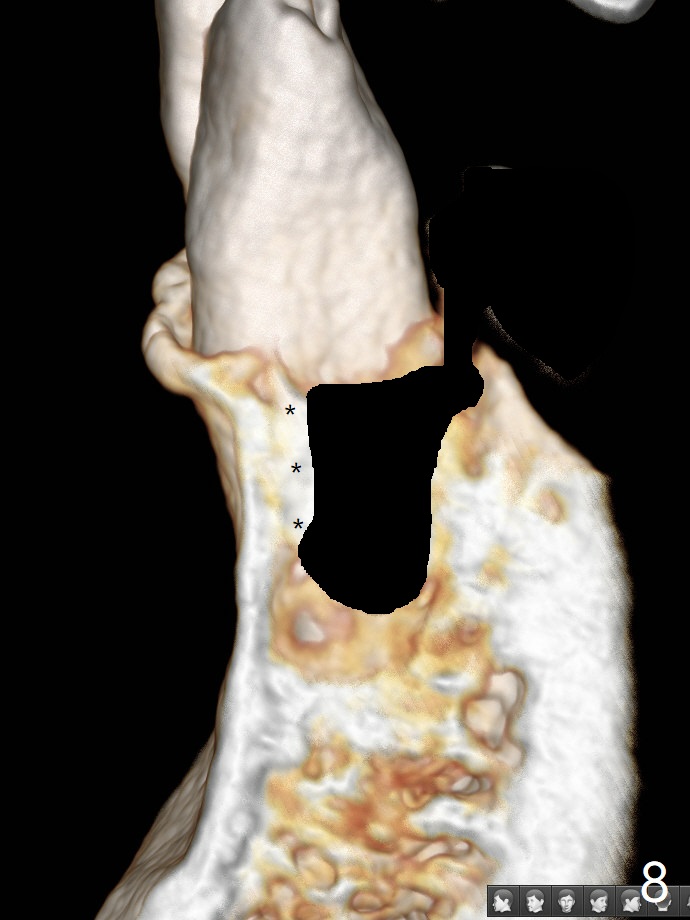

A 52-year-old man chooses to take care of the teeth #21 and 29 first due to finance (Fig.1). The implant diameter should not be too large because of the moderate mesiodistal space (Fig.2,3). Since the buccal plate of #21 is indistinct (socket shield will be done), the implant should be a little more lingually placed than the design in Fig.3, although the implant placement level seems to be acceptable. Socket shield seems to be necessary.